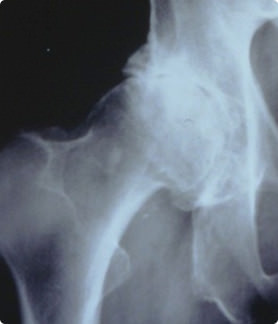

股関節は、大腿骨の丸い頭の部分(大腿骨頭)が骨盤の受け皿の部分(寛骨臼)にはまり込んでいます。関節部分の骨の表面は軟骨でおおわれ、股関節にかかる力を吸収するとともに大腿骨頭と寛骨臼の動きをスムーズにしています。

罹患者は日本全国には300~400万人くらいいると言われています。原因としては、子供の頃の発育性股関節形成不全の後遺症や、股関節が浅い寛骨臼形成不全などが多いですが、加齢により股関節の軟骨がすり減ってしまうことが原因になることもあります。

特発性大腿骨頭壊死症とは、大腿骨頭の一部が、血流の低下により壊死に陥った状態になる病気です。

この病気は、骨壊死が発生するだけでは痛みは出ません。骨壊死に陥った部分が潰れてしまうことにより、股関節の痛みが出現します。骨壊死はあっても、壊死した部分が潰れなければ痛みは出ません。